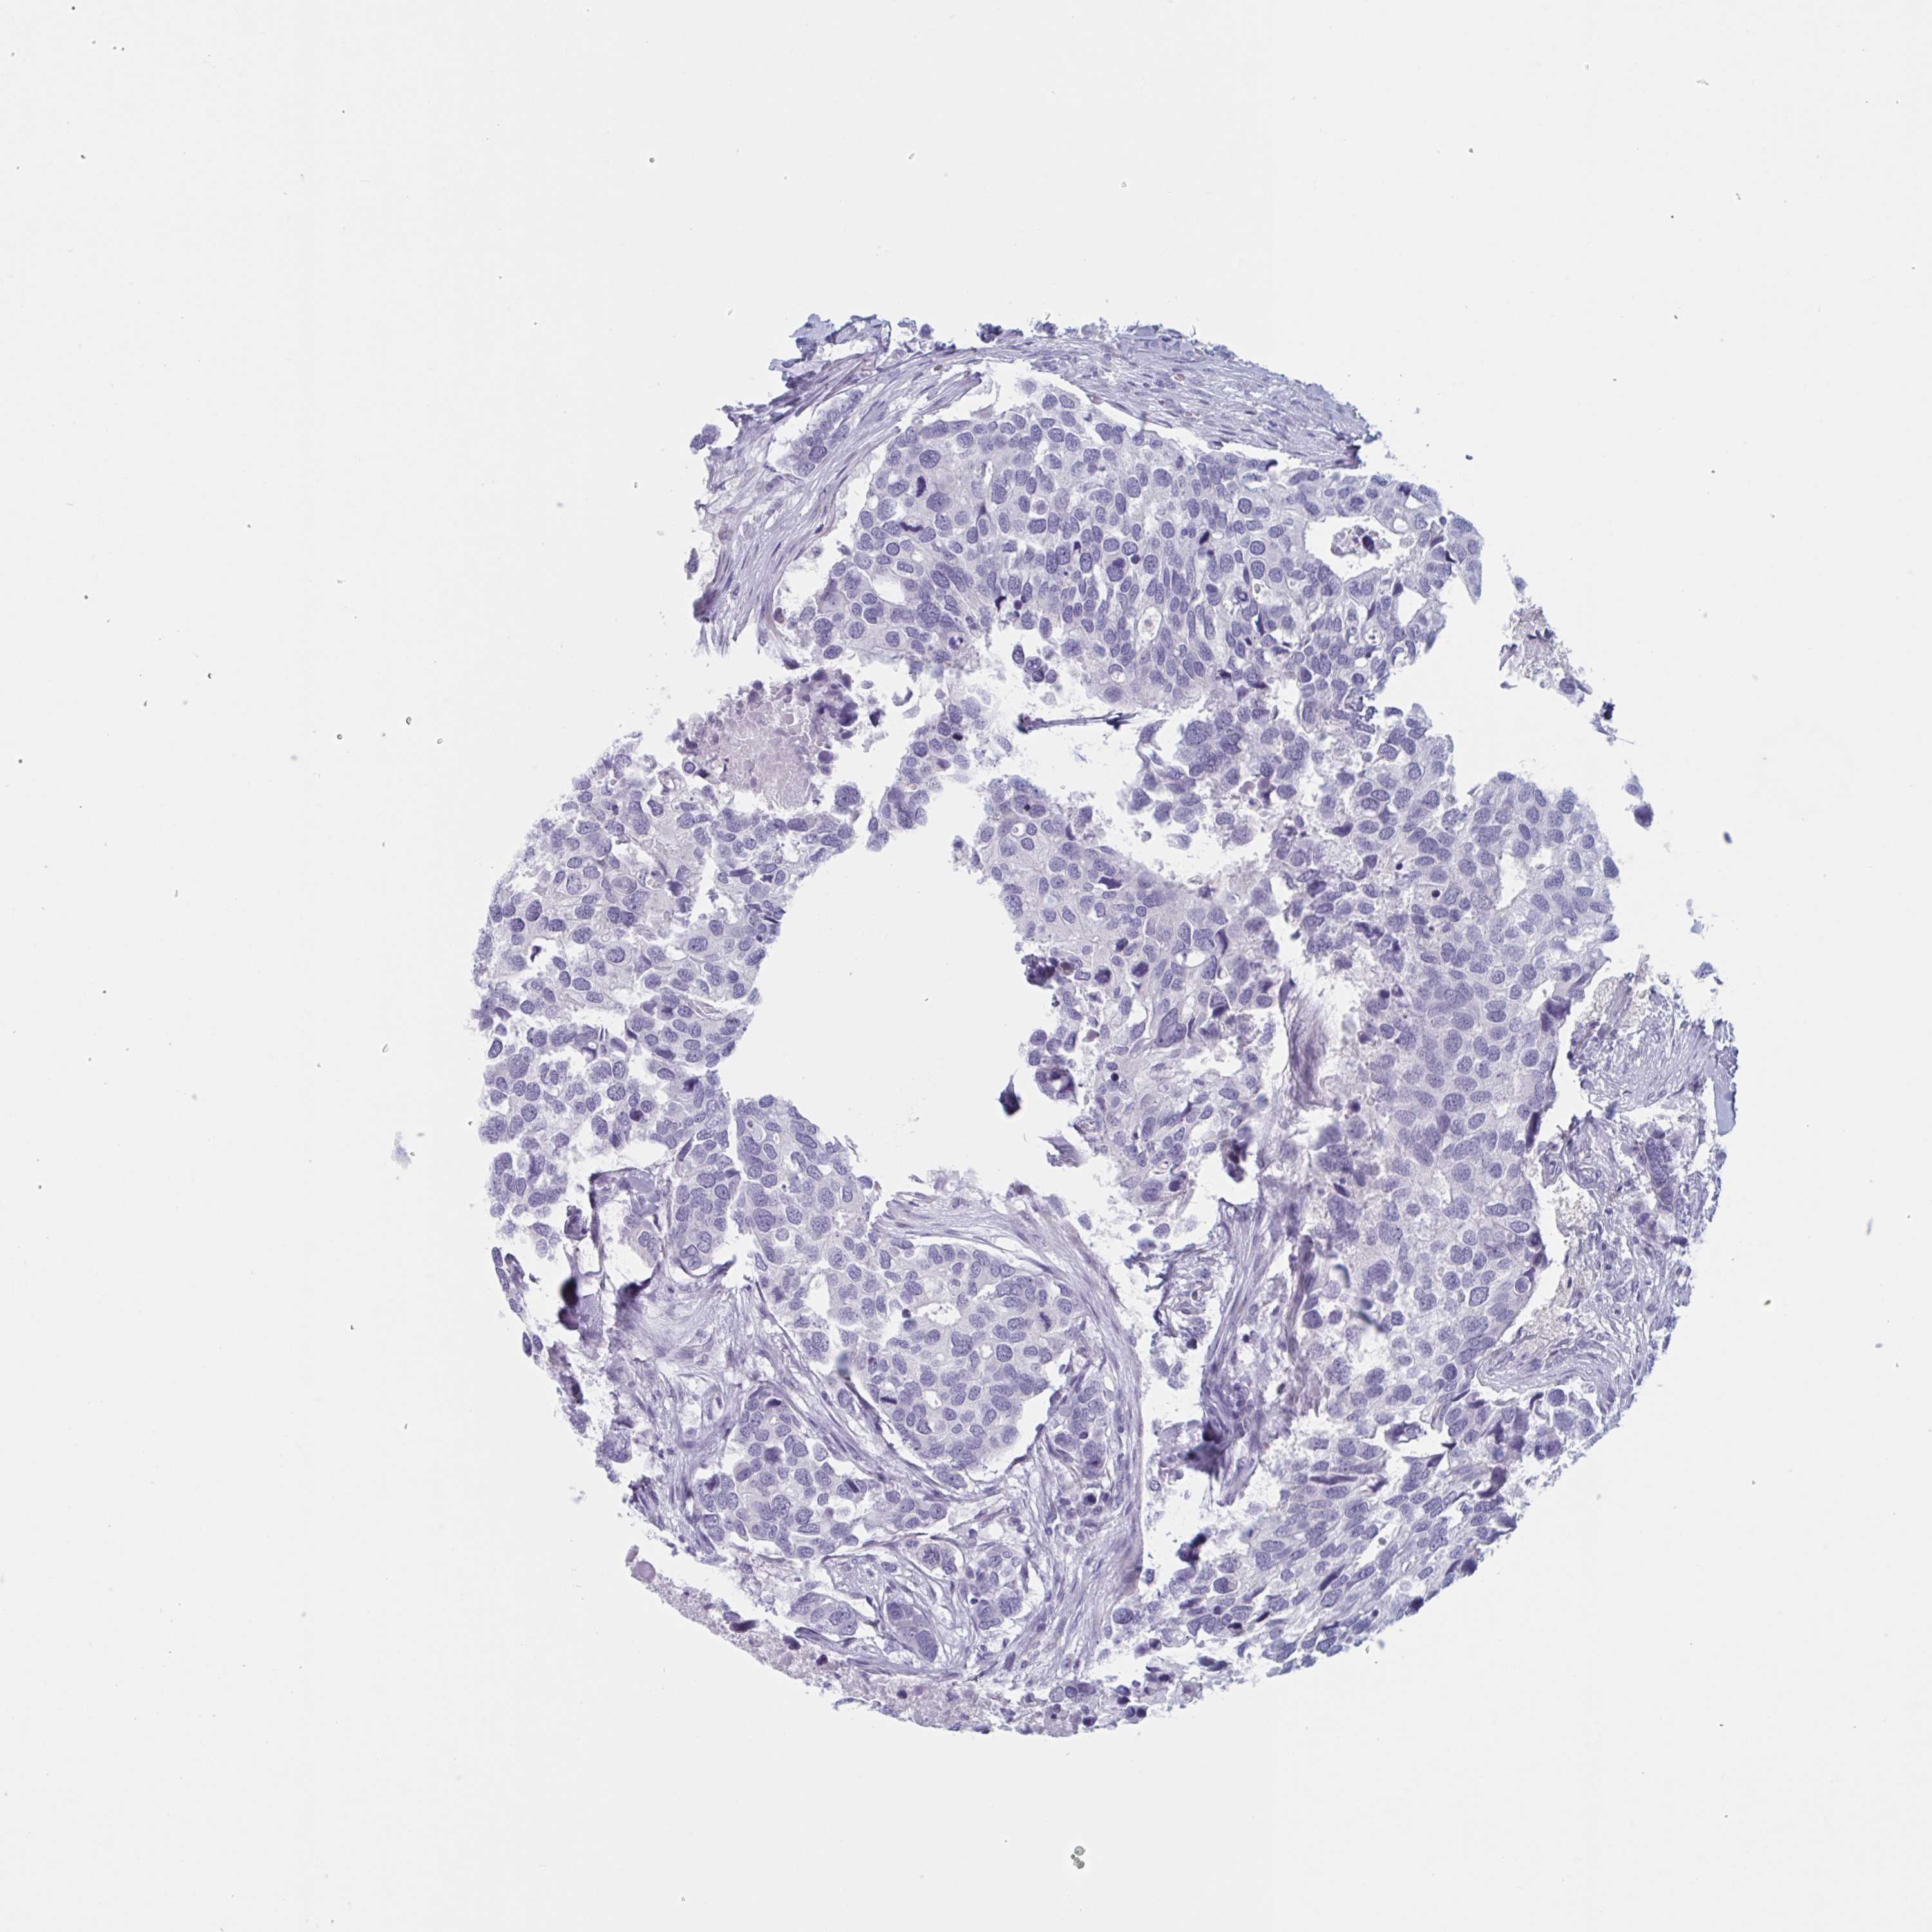

CANCER BREAST CANCER Show tissue menu

BRCA TCGA BRCA VALIDATION PROTEIN EXPRESSION